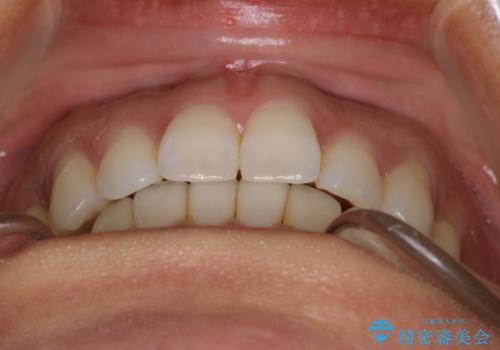

【インビザライン】前歯をきれいな歯並びにしたい

- 前歯の叢生を主訴に来院されました。このケースは抜歯をせずにIPRにてスペースを確保し、並べる計画をたてました。

きちんと使用時間を守って使用していただいたことで短い期間で治療が終了しました。